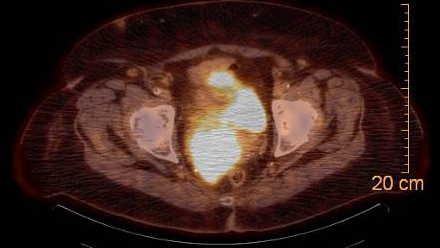

76 yr old female with stage IVA cervical squamous carcinoma with PA and right pelvic nodes, mesorectal pelvic nodes as well as right hydronephrosis, bilateral parametrial involvement and rectal wall invasion without a definite fat plane at the lower cervical mass. Definitive chemoradiation with cisplatin, immunotherapy and radiation was recommended after a multidisciplinary discussion.

Figure 1: PET/CT with mesorectal invasion and parametrial invasion